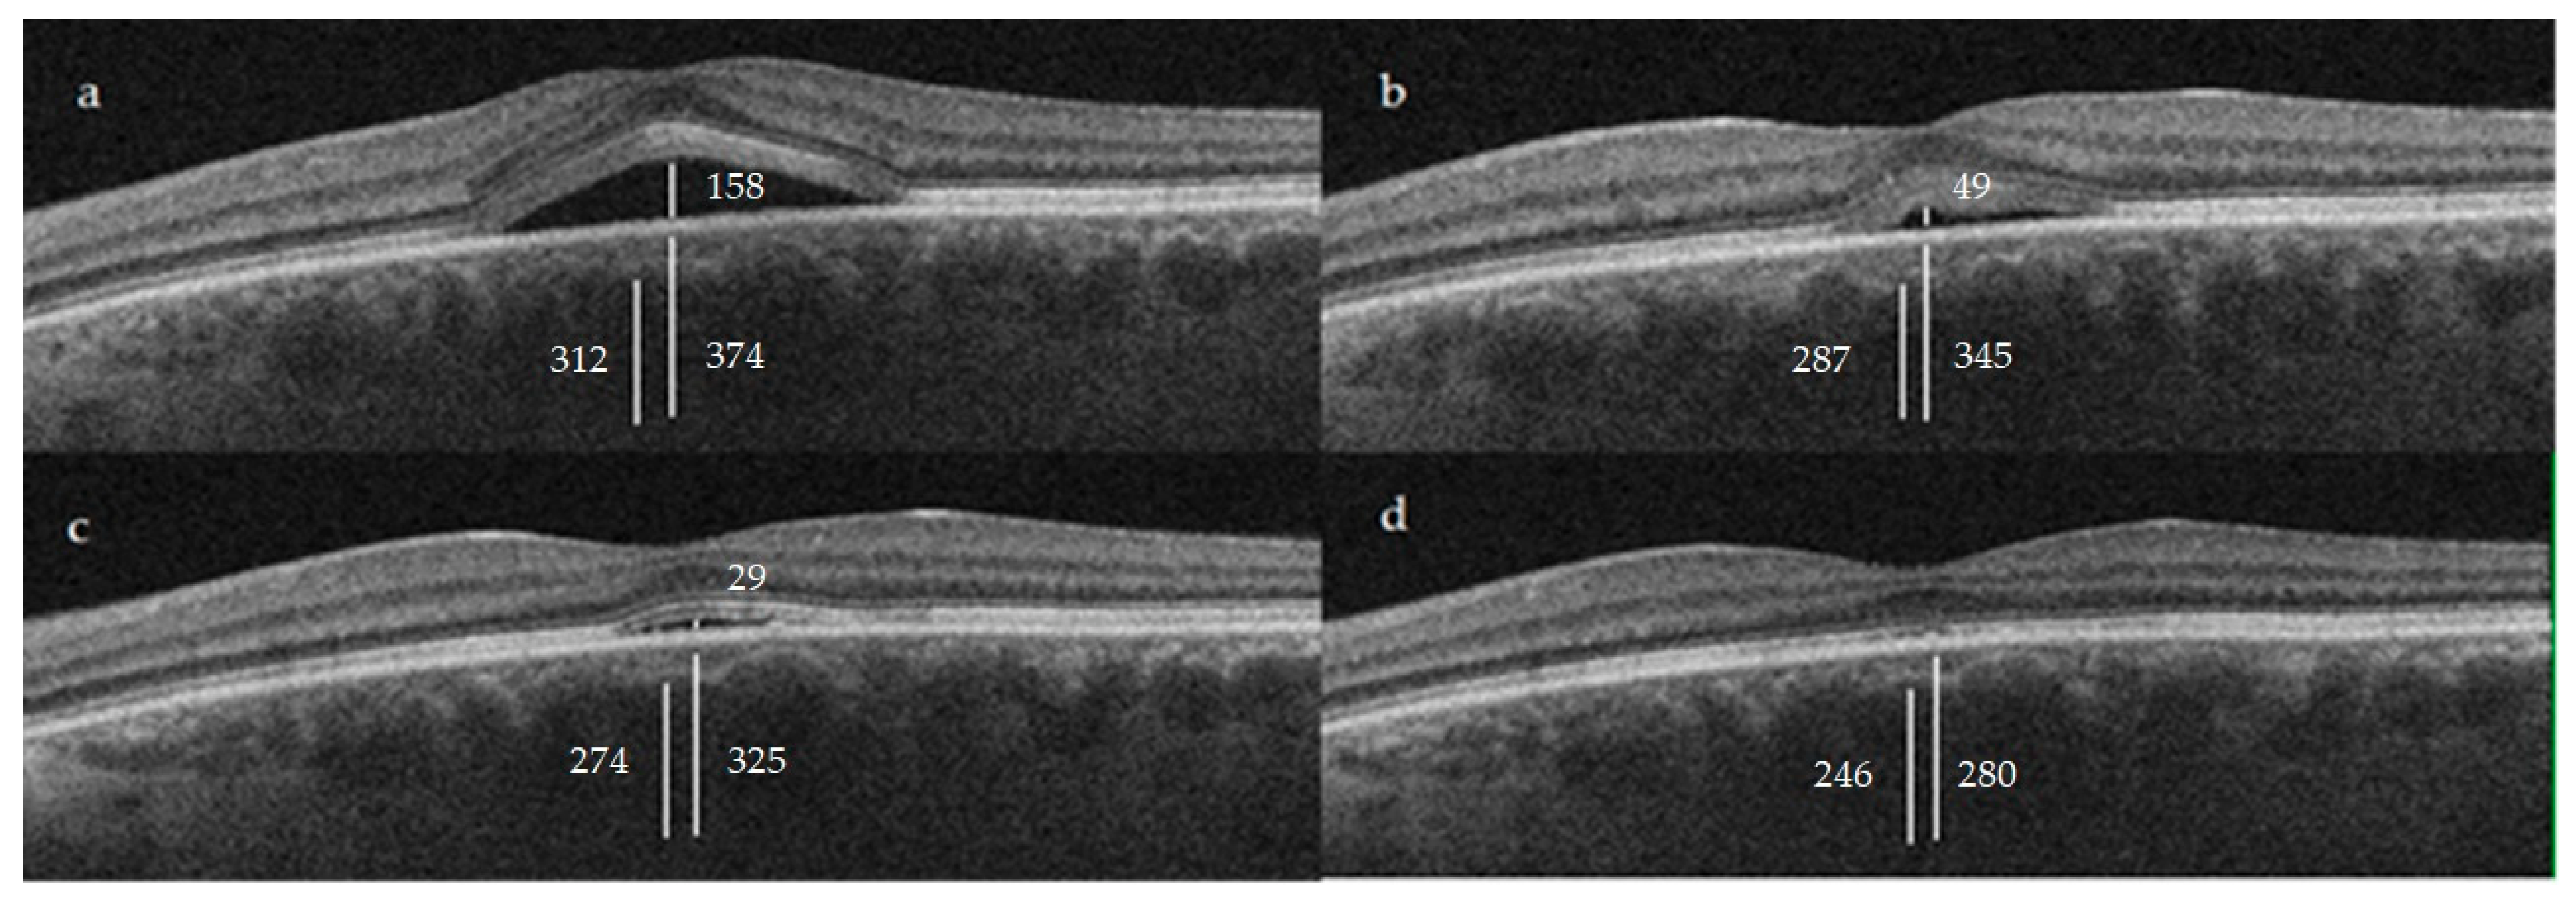

| CT | 374.9 ± 81.1 | 345.3 ± 71.5 | 0.0566 | 325.8 ± 59.2 | <0.05 | 280 ± 114.6 | <0.05 |

| Haller layer | 312.1 ± 71.3 | 287.4 ± 64.3 | 0.0953 | 274 ± 55.1 | <0.05 | 246 ± 115.9 | <0.05 |

| C-S | 62.8 ± 23.9 | 57.93 ± 20.8 | 0.3164 | 51.8 ± 18.3 | <0.05 | 34 ± 20.8 | <0.05 |

3.3. Choroidal Thickness (CT)